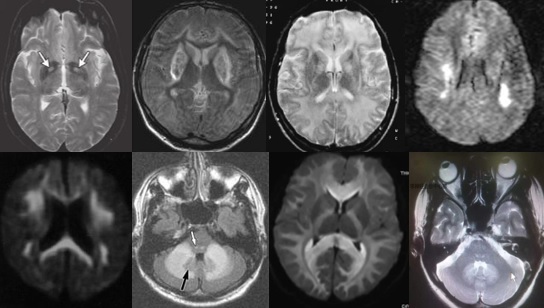

重要申明:以下每个部分会配磁共振图片,因疾病和影像之间存在同病异象、同像异病,为避免误导,图片不标注疾病,请各自鉴赏,另其中有部分图片来源于网络,有疑问可与本人联系。

H--hereditary,遗传

引起中枢神经系统病变的遗传性疾病可是种类繁多,主要指脑白质营养不良、脑小血管病等白质受累为主的病变。

如前者按发病机制可分为:溶酶体疾病(异染性脑白质营养不良、Fabry’s 病、Krabbe’s 病),过氧化物酶疾病(肾上腺脑白质营养不良(ALD)、肾上腺脊髓神经病(Adrenomyeloneuropathy))、线粒体疾病(MELAS、Leigh病)。按髓鞘病变病理过程种类分:异常髓鞘化:肾上腺脑白质营养不良、球形细胞脑白质营养不良、 染性脑白质营养不良;髓鞘化低下:佩梅氏病、Alexander病、白质消融性脑白质病;髓鞘囊性变性:Canavan病、空泡性脑白质病。

各种遗传性脑小血管病:如CADASIL、CARASIL、Fabry病及CAA、CAA相关性血管炎等等。

还有结节性硬化、各类NBIA(脑组织铁沉积神经变性病),脑肝肾综合征、线粒体脑病、LCC等。